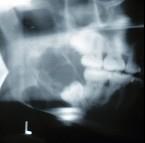

某患者一侧下颌磨牙区、下颌角及升支部渐进性膨大,按之有乒乓球感。X线片(如图)示多房性密度减低影,分房大小相差悬珠,分隔清晰锐利、阴影边缘呈切迹状,阴影内牙根尖有不规则吸收。该病最可能的诊断是 ( )